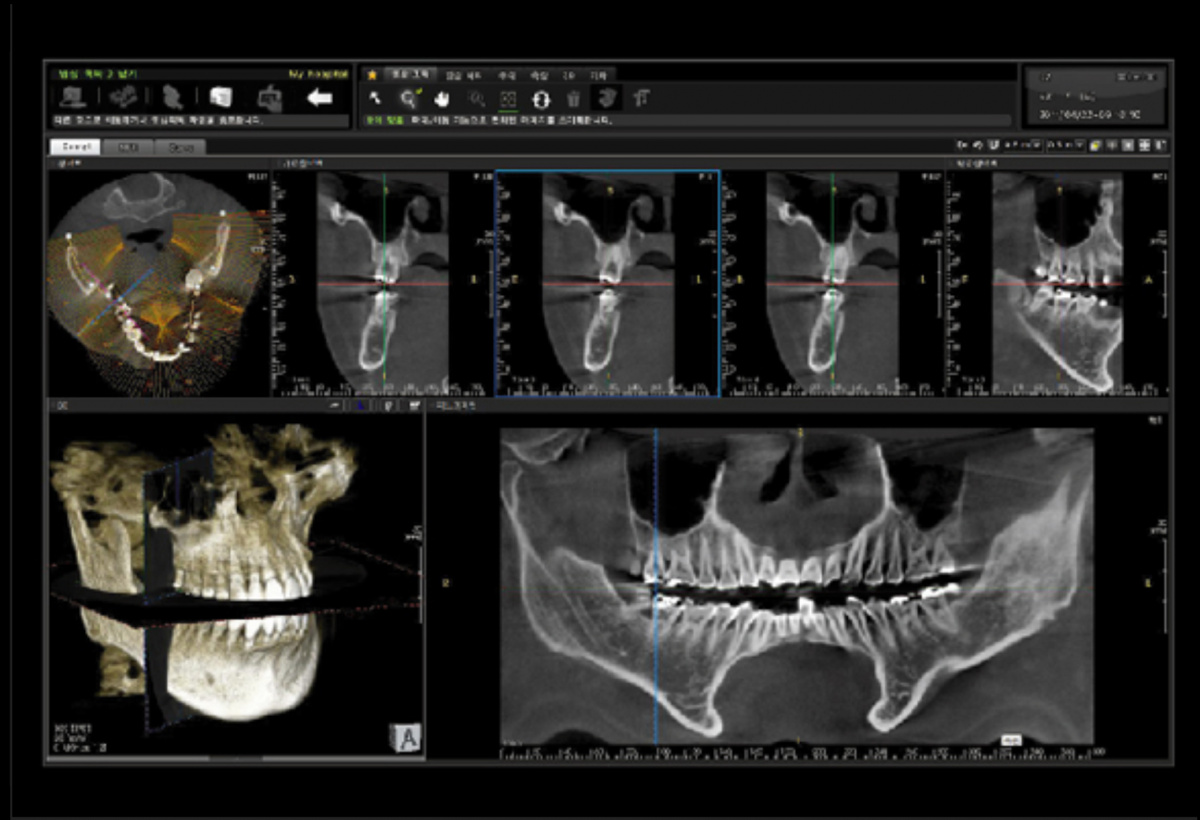

Немаловажным, а может главным вопросом, является универсальность программы-просмотровщика, в которой будут работать врачи-стоматологи. У Papaya 3D есть два варианта программ: Triana и OnDemand3D. Оба просмотровщика обладают схожим интерфейсом и имеют самые важные опции, а именно:

• режим MPR (многоплоскостная реконструкция). Именно здесь выстраивается интересующий участок челюсти или зуба для анализа.

• панорамный реформат. Возможность постройки классической и сегментарной панорамы позволяет продемонстрировать план лечения пациенту, а также оценить расположение анатомических структур на боковых кросс-секциях.

• модуль дентальной имплантации. Возможность виртуальной установки дентального имплантата с анализом окружающей костной ткани. В библиотеке представлен широкий спектр имплантологических систем с индивидуальной прорисовкой имплантата.

• выделение нижнечелюстного канала позволяет продемонстрировать расположение важного анатомического образования и определить зону безопасности при проведении лечения.

• функции плотности, линейных измерений и угла – необходимы для получения полноценной информации для последующего лечения.

• 3D режим – показывает трехмерную модель челюсти с целью определения аномалий, деформация, а также визуализации виртуальных имплантатов.

Таким образом обе программы являются простыми в пользовании, но обладающими обширным спектром возможностей для диагностики любыми специалистами-стоматологами. В данные программы происходит загрузка классических файлов DICOM 3.0, которые являются общепринятым форматом записи данных пациента. Это важный момент, так как позволяют врачу, имеющему полную версию программы загружать даже сторонние исследования и просматривать их в этих программах. Простота в освоении этих программ позволяет даже специалисту, не работающему раннее с этими программами, быстро адаптироваться и получить качественную информацию. Возможность выгрузки STL-файла дополнительно создает возможность интегрировать данные с цифровым ортопедическим протоколом.